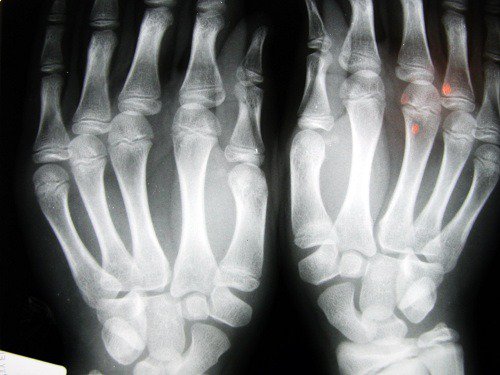

Om ditt pekfinger är kortare än normalt beror detta antagligen på att dina nivåer av testosteron är högre, oavsett om du är man eller kvinna. I nästan alla fall är längden på pekfingret kortare än ringfingret hos män, medan kvinnor har ungefär samma längd på dessa fingrar.

I en studie gjord vid University of Nottingham i Storbritannien visade det sig att personer vars pekfinger är kortare än de andra fingrarna löper risk för att utveckla problem som osteoartrit. Detta problem har att göra med en brist på östrogen och för lite fysisk aktivitet, något som speciellt påverkar kvinnor.

En studie från University of Warwick visade att män som har ett längre pekfinger än ringfinger löper en tredjedel mindre risk för att drabbas av prostatacancer i framtiden, jämfört med de som har ett längre ringfinger.

Om pekfingret är längre än ringfingret kan detta indikera att personen har blivit utsatt för höga nivåer av testosteron under fostertiden. King’s College i London har gjort en studie som visade att hormonexponering i livmodern kan påverka framtida beteende.